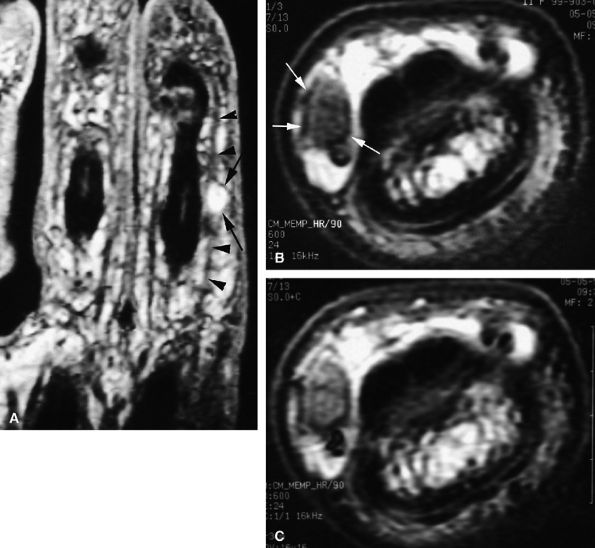

FIGURE 11.34 ● Complete rupture of the central slip of the extensor tendon on sagittal (A) and axial post-enhanced T1-weighted images at the level of the PIP joint space (B) and the distal third of the proximal phalanx (C). There is distal avulsion of the central slip with a tendon gap (arrows) and limited retraction. The proximal end is thickened and shows signal heterogeneity (asterisk).

central slip and a lateral band of the extensor tendon may occur in cases of additional rotational trauma. Chronic symptomatic lesions require surgical reconstruction.55,57